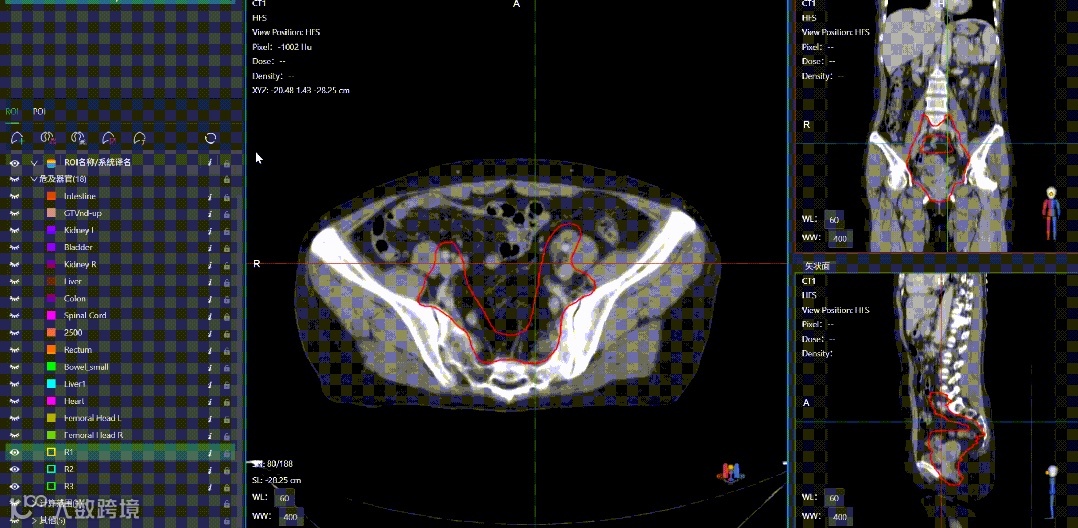

uTPS中的ROI模板中也带了一个类似的机制,能让ROI在逻辑关系上产生关联。下图可以看到,ROI模板中保存的信息并不只有ROI的名称、颜色等属性,还有ROI的生成方式,这其实是个强大的钩子。

uTPS中ROI的生成方式有三种,智能分割生成、手动生成、函数生成,这些信息会被存到模板中。当调用这个模板时,里面的ROI会根据生成方式来还原生成过程:

智能分割支持显示为“是”的ROI,在调取使用模板时会去调用对应的勾画模型做智能分割。智能分割支持为“否”的ROI,则生成空的结构。